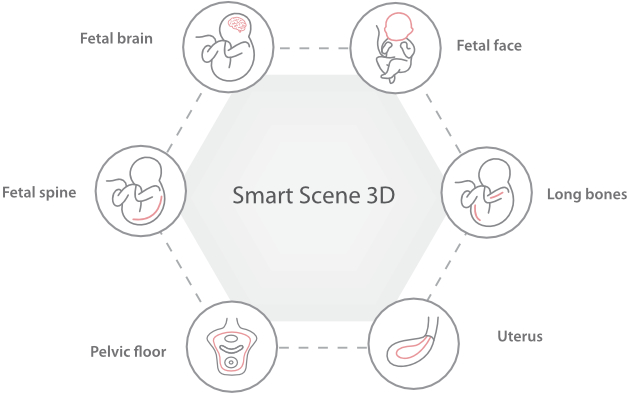

Nuewa I9, kad?nlara ve yenido?anlara y?nelik sa?l?k hizmetleri i?in ?zel olarak tasarlam??t?r ve i?ten d??a yenilik?i bir deneyim sunmaktad?r. Bu yenilikler, karma??k klinik senaryolara ili?kin derinlemesine bilgilere dayal? olarak geli?tirilmi?tir ayr?ca do?ru ve zaman?nda yan?tlar?n yan? s?ra, ola?an├╝st├╝ verimlilik ve ola?an├╝st├╝ kullan?c? deneyimi sunar.